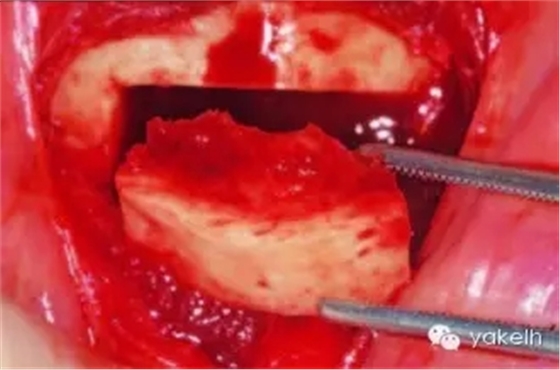

¤¤暴露頦部后,設(shè)計(jì)取骨的切口。取骨塊的大小由受區(qū)所需的骨量決定。骨切開處距離根尖以及頦孔最少應(yīng)有5mm。多數(shù)情況下,要保留下頜骨下緣以及舌側(cè)皮質(zhì)骨的完整性。唇側(cè)皮質(zhì)較厚,其內(nèi)側(cè)的松質(zhì)骨通常較致密??梢允褂脺u輪手機(jī)碳合金裂鉆(557號(hào)或701號(hào))或者來復(fù)鋸將骨切開(圖13.19)。切透皮質(zhì)骨達(dá)松質(zhì)骨后,用骨鑿將骨塊移除(圖13.20)。用單面鑿沿著骨切開線輕輕敲擊,除了下頜骨下緣,將骨塊從基底部折斷。在中線處時(shí),也可將塊狀骨分割成矩形骨塊,分段獲取。分成兩個(gè)骨塊后更容易獲取,因?yàn)榭梢杂霉氰弻⒌诙K骨塊從舌側(cè)撬起。另外,移除塊狀骨后,還可使用骨刮匙、鑿子、咬骨鉗、環(huán)形鉆獲取

一些松質(zhì)骨,但是松質(zhì)骨的量十分有限。在移除塊狀骨后,可以將止血材料如膠原或明膠海綿置于松質(zhì)骨表面。當(dāng)獲取較大的骨塊時(shí),供區(qū)應(yīng)使用骨替代材料如羥基磷灰石,來維持唇側(cè)的外形(圖13.21)。較少或者顆粒狀的骨移植時(shí),可使用環(huán)形鉆、骨收集器、骨挖器來獲取。把骨塊植入受區(qū)后,再將供區(qū)的傷口縫合,這可以縮短取骨與植骨之間的時(shí)間。分離前庭溝切口上方的黏膜,以減少水腫和下唇運(yùn)動(dòng)所產(chǎn)生的張力。用可吸收縫線分層縫合前庭溝切口(圖13.22)。深層組織使用4-0可吸收線縫合,表層黏膜使用4-0鈷腸線縫合。術(shù)后使用壓力繃帶包扎頦部,以減少水腫、血腫形成及切口裂開(圖13.23)。

圖13.20 從頦部獲取厚的皮髓質(zhì)骨塊。